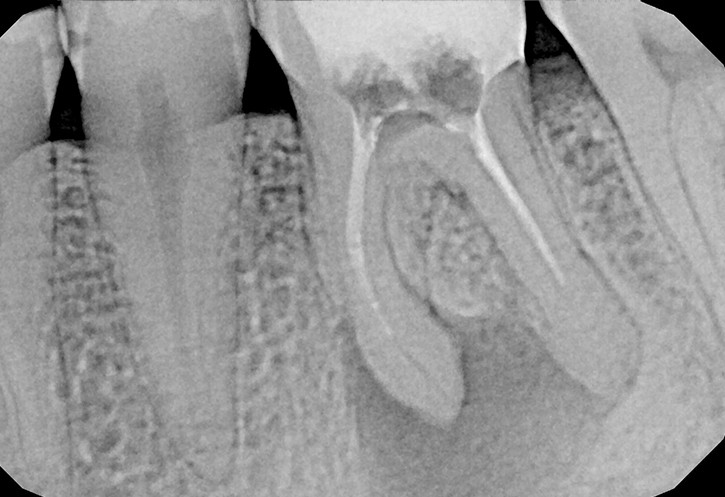

W przypadku zaawansowanych postaci zapaleń miazgi oraz zapalenia tkanek okołowierzchołkowych obraz radiologiczny jest warunkiem rozpoznania. W takiej sytuacji standardem diagnostycznym są zdjęcia przylegające zęba, często wykonywane przy użyciu radiowizjografii na fotelu stomatologicznym w trakcie leczenia zęba. Przydatne jest również badanie RTG OPG pantomograficzne, które pokazuje w dwuwymiarowym obrazie zarówno uzębienie, jak i cały układ kostny szczęki oraz żuchwy.

Stożkowa tomografia komputerowa CBCT, ze względu na dokładne, trójwymiarowe obrazowanie 3D, bez zniekształceń ukazuje szczegóły anatomii zęba oraz okolicznych tkanek, wyjaśniając nierzadko problemy niemożliwe do zdiagnozowania standardowymi metodami.